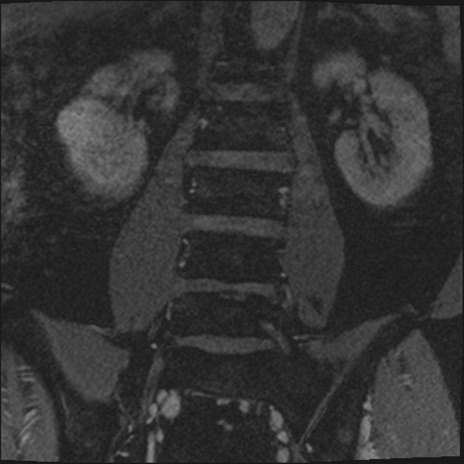

【整形】TIPS症例2 腰椎MRI 3D(冠状断像)

【症例】70歳代男性

【主訴】左下肢痛

【現病歴】2週間前くらいから腰痛、左下肢痛あり。左臀部から大腿、下腿外側のしびれが常時ある。歩行とともに同部位の痛みあり。

【身体所見】Lasegue70-/60+、Bragard-/±、PTR ±/±、ATR -/-、IP 5/5、TA 5/4、TS 5/5、EHL 右第1足趾なし/3、FHL 5/5、hypersthesia(-)、足背動脈触知良好

異常所見と診断は?